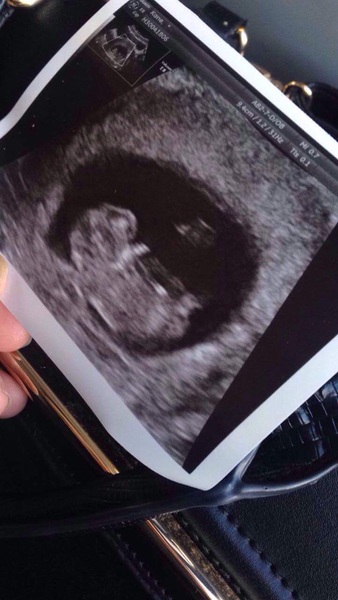

This is my scan! It was at 10 weeks though not 12 x

Lovely scan pic Pugs. Congratulations!